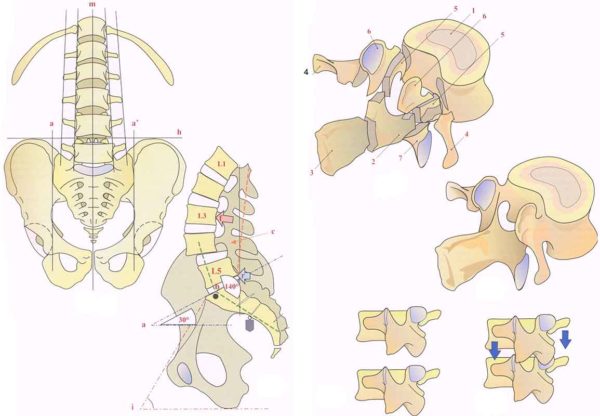

Поясни́чные позвонки́ (лат. vertebrae lumbales) — пять нижних позвонков у человека с 20-го по 24-й, считая сверху. Поясничный отдел позвоночника соединяется ниже с крестцом (нижний поясничный позвонок L5 соединяется с верхним крестцовым позвонком S1), выше — с грудным отделом позвоночника (L1 соединяется с нижним грудным позвонком Th12).

Особенности анатомии[править | править код]

Тело поясничного позвонка больше в ширину, чем спереди назад. Ширина больше высоты.

От тела позвонка назад идёт дуга, замыкающая позвоночное отверстие и переходящая далее в остистый отросток. На плоскости дуги в обе стороны расположены поперечные отростки, которые являются рудиментами рёбер. У основания поперечных отростков поясничных позвонков заметен рудимент истинных поперечных отростков (processus accessorius), который при большой длине (4 мм) приобретает форму шила (processus styloideus). Авторы М. Г. Привес, Н. К. Лысенков, В. И. Бушкович замечают, что его не следует принимать за патологическое образование. На верхней и нижней гранях дуги расположены парные верхние и нижние суставные отростки. В четырёх верхних поясничных позвонках остистые отростки направлены прямо назад, суставные расположены сагиттально. Позвоночные отверстия, начиная со второго поясничного позвонка, постепенно сужаются, что связано с анатомией спинного мозга.

Тело пятого поясничного позвонка в направлении к остистому отростку имеет клиновидную форму, при этом оно наклонено вперед, так как крестцовая кость направлена назад, формируя кифоз. Суставные отростки размещены в полуфронтальной, полусагиттальной плоскостях.

Функции[править | править код]

Поясничные позвонки образуют поясничный лордоз. Поясничный лордоз формируется во время освоения ребёнком положения стоя и ходьбы. На поясничный отдел позвоночника выпадает самая выраженная амортизирующая функция. К старости эта функция ослабляется.

Поясничные позвонки наиболее массивные и крупные во всём позвоночнике, с увеличением от первого поясничного к пятому, что объясняется максимальной нагрузкой на нижний отдел позвоночника. Позвонки грудного отдела и крестец малоподвижны, что требует от позвонков поясничного отдела повышенной подвижности. Пять поясничных позвонков человека и крестец образуют пять позвоночно-двигательных сегментов, что обеспечивает принципиальную возможность поворотов корпуса в стороны, движений корпуса в сагиттальной и фронтальной плоскости, а также комбинированные повороты и наклоны. Наличие сильных мышц поясницы помогает осуществлять движения даже с дополнительной нагрузкой.